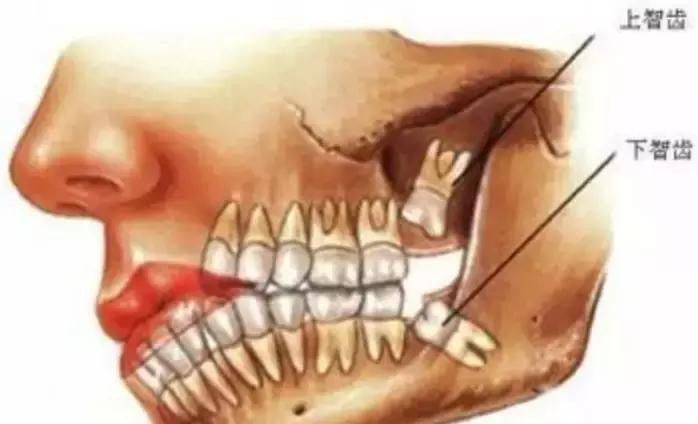

啥叫智齿?

智齿是人类的第三磨牙,也是口腔最靠近喉咙的牙齿,如果全部生长出来一共4颗,上下颌各两颗。由于它最晚长出,一般在18岁后开始萌出,是心智成熟的标志,所以被俗称为“智齿”。

有关调查表明:

我国16—25岁人群中智齿的萌出率为54%,在已萌智齿中阻生和错位约占44% ,其中发生在下颌者约是上颌者的2.5倍。